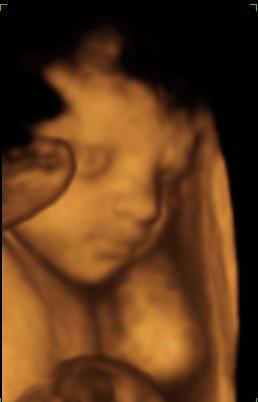

A doki szerint pufók kislány